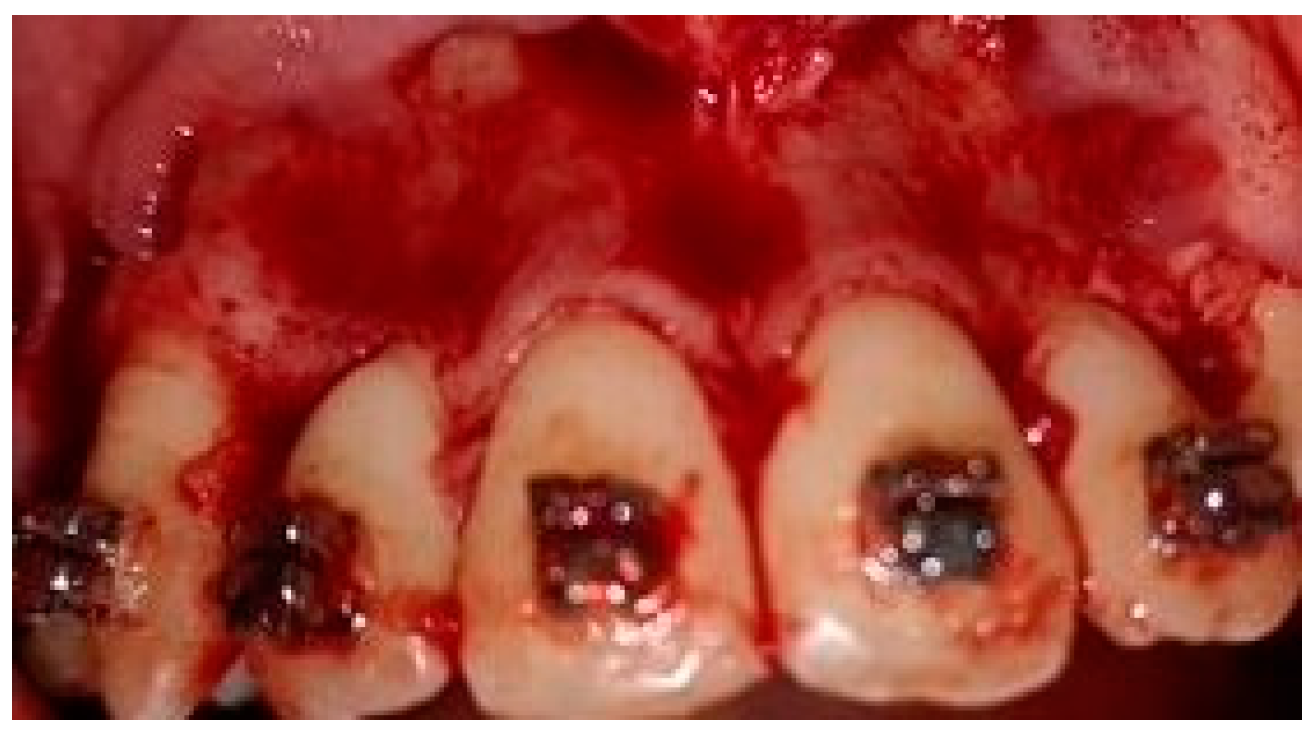

2.5. Surgical Phase

2.6. Collection of the Radiological Data